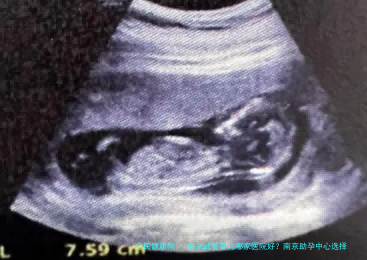

南京试管婴儿哪家医院好?南京助孕中心选择要注意什么?

南京我们试管机构医院是南京较大且受欢迎的助孕公司之一。作为一家生殖医院,它具有先进设备和专业医学人士集体,能够提供全方面、个性化的助孕服务。此医院提供多种不孕不育治疗计划,如试管婴儿、人工授精和胚胎保存等。再者他们还提供生殖医学中心和母细胞体库服务,帮助那些需要助孕或卵子来实现梦想的夫妇。

南京聚缘生殖医院是另外一家备受推崇的助孕企业。他们具有国内赫赫有名的生殖专家团队,并与多个国际有名气生殖中心协同,汇聚了在国际上先进的技术和设备。此医院提供试管婴儿、助孕、胚胎保存等多种不孕不育治疗方案。

南京馨怡助孕期内心是一家综合性辅助生育机构,提供试管婴儿、人授、助孕等多种不孕不育医治策略。该中心拥有一支经验丰富的医疗集体,能够根据患者的详细情况订定个体化的治疗方案。